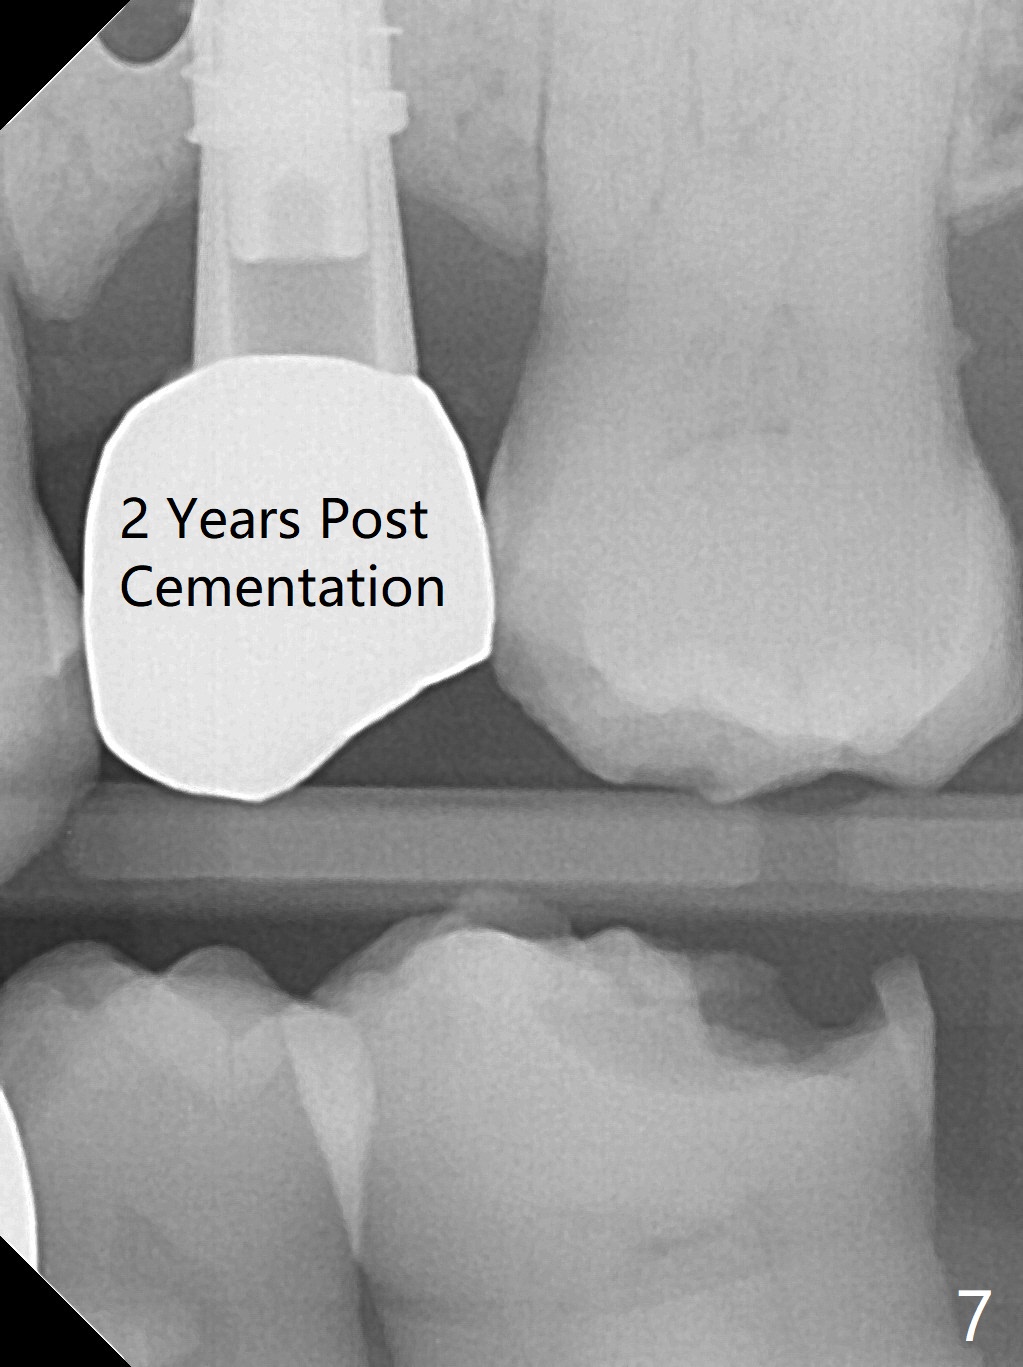

A 74-year-old man has diabetes. Implant osteointegration appears to be slow at #4, while the implant at #28 failed once. He requests implant at #13 (Fig.1). It seems that the bone is wide enough (8 mm, Fig.2 (CT coronal section) (P: palatal)) to hold a 4 mm implant (Fig.3 (axial section)). Since bone density is low at the coronal (100-200 units) and middle (50-100 units) segments (Fig.2), bone condensation will be beneficial. To facilitate wound healing, flapless approach is adopted using 1.6 mm pilot drill (Fig.4), followed by 1.4/2.6 mm bone expander. In fact there is resistance to expansion in the zone 1. Magic expander (3.0 mm) is also tried with difficulty. It appears that bone density is higher than expected. The second portion of Magic Surgical Kit is then used: 3.3 mm Magic Drill for 15 mm (gingival level, followed by Final Drill). A 4x13 mm IBS implant is seated incompletely. The osteotomy is further enlarged by 3.8 mm Magic Drill for 11 mm and deepened with 3 mm drill until 18 mm. Finally the implant is placed at a satisfactory level with insertion torque > 50 Ncm (Fig.5). A 4.5x4(3) mm abutment is placed and periodontal dressing is applied. The patient chooses to return for impression 6 months postop (Fig.6). The abutment changes to a 4x4(4) mm one. The crown is recemented nearly 2 years post cementation, which is related to distal and deep placement of the implant and bruxism (Fig.7).